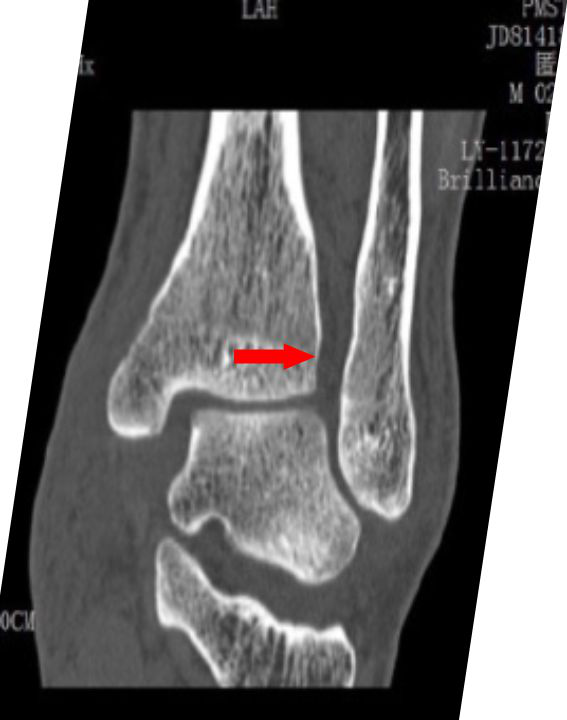

· CT 检查可以更完善了解腓骨交锁于胫骨后方的位置、程度以及骨折线走行,同时可了解其他微小骨折、后踝骨折及下胫腓联合的关系;